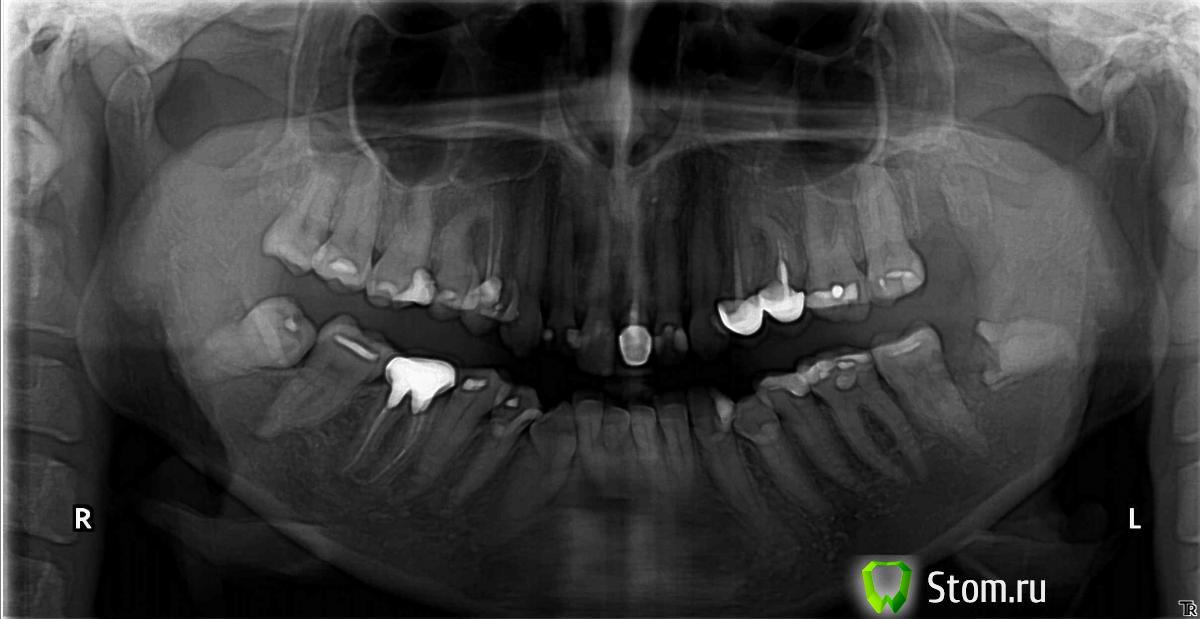

Аслан Опубликовано 20 апреля, 2012 Поделиться Опубликовано 20 апреля, 2012 Пациент Д. 20 лет. Обратился с жалобами на боли в области зубов всех. Вдаваться в подробности не буду. Жутчайший ювенильный пародонтит. В полости рта аж закаменелые сгустки крови из карманов, местами серые, как при альвеолите сгусток. Ну и конечно же запах изо рта. Сделал гигиену, сейчас вроде все получше. Есть фотки до гигиены и после гигиены сразу и через неделю. Если будет интересно выложу позже. Так как у него есть еще и ортодонтическая пвтология, решили с шефом аккуратно провести через ортодонтию. Предварительно хирургическая подготовка, удаление 8ок всех. http://s019.radikal.ru/i607/1204/f1/ddd11f5bd7abt.jpg 18, удаление около 1 минуты. Все прекрасно.Через неделю 28, 10 секунд + 2 минуты анестезия. Пац в шоке, что так быстро. Сегодня 38.38, медиально наклонен, среднее залегание, отношение к каналу - по этому снимку я постчитал что канал вестибулярнее медиального корня. Сложность удаления средняя, ориентировочное время 40 минут. А в итоге. Когда убрал десну. Залегание глубокое, в ретромолярке и вестибулярно толстенная кортикальная кость миллиметра 3. Убрал навесы из кости, Попробовал достать целиком, не поместился. Спилил медиальные бугры. Как мне показалось. Нет подвижности. Работа осложняется тем, что один, у пациента маленькая ротовая щель, и пылесосная труба постоянно засасывает слизистую вместо содержимого (крови и слюны, и подтянула помоему даже кусочек околоушной слюнной железы, я его аккуратно на место заправил в конце, но он так и наровил в трубу улететь (((((. ). 3 часа работы. Потом взял самый длинный бор который только нашел. Сделал новый распил еще глубже. 10 минут. Прямым элеватором отколол отпиленное, достал. 3 минуты, Далее прямой элеватор, 30 секунд и все. Зуб удален. Казалось бы все. Изучаю зуб. И очень удивился наличию желобка на изгибе медиального корня. Бысренько заглянул в лунку, просушил, а там вроде все чистенько и на дне даже сгусток кровяной уже образовался. Не полез туда ковыряться. Просто ушил десну. Завтра контрольный осмотр.http://s018.radikal.ru/i513/1204/14/57fae80440b4t.jpghttp://s019.radikal.ru/i641/1204/b7/9dba3161e4aet.jpg Мои ошибки. Надо было КЛКТ сделать. Надо было сразу длинный бор брать. Зуб справа. (48) либо клкт, либо оптг и в стационар. Он точно корнем в канале. И минимум через месяц. Ссылка на комментарий